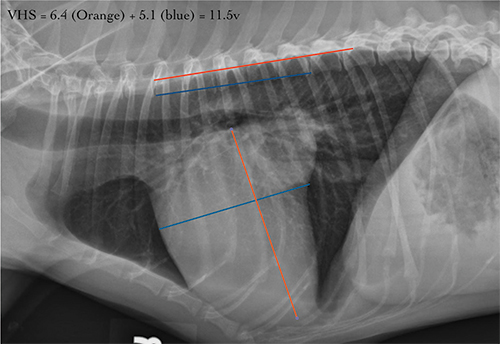

Figure 3 – VHS (moderate cardiomegaly in a dog with a VHS of 11.5) measurement technique on lateral thoracic radiograph demonstrating how to measure the long and short axis of the heart and compare to vertebral bodies starting at T4.

Reference and image credit: https://vetmed.illinois.edu/2022/07/06/evaluating-the-heart-size-on-radiographs/

| Measurement | Normal Value | Significance |

|---|---|---|

| Vertebral Heart Score (VHS) | 8.4-10.5 vertebrae (dogs) | Greater than 10.5 suggests cardiomegaly Greater than or equal to 11.5 = Stage B2 criterion |

| Vertebral Left Atrial Size (VLAS) | 1.8-2.3 vertebrae | Greater than 2.3 indicates LA enlargement More specific than VHS for LA size |

- Figure 3: VHS measurement technique. Source: University of Illinois College of Veterinary Medicine - "Evaluating the Heart Size on Radiographs" - Figure 1. Available at: https://vetmed.illinois.edu/2022/07/06/evaluating-the-heart-size-on-radiographs/ (Educational institution - free access)